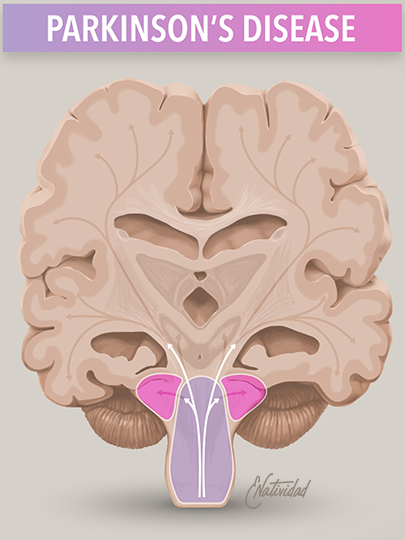

Running series of animated visual abstracts, Quick Takes, created for The New England Journal of Medicine as part of a team of illustrators, medical writers, and scientists. These short, iconographic animations aim to succinctly describe clinical trials and increase the awareness and understanding of important research findings.

Adopting The Journal’s visual style and asset library, I am responsible for the entire production process including narration editing, storyboarding, layout, illustration, and animation.